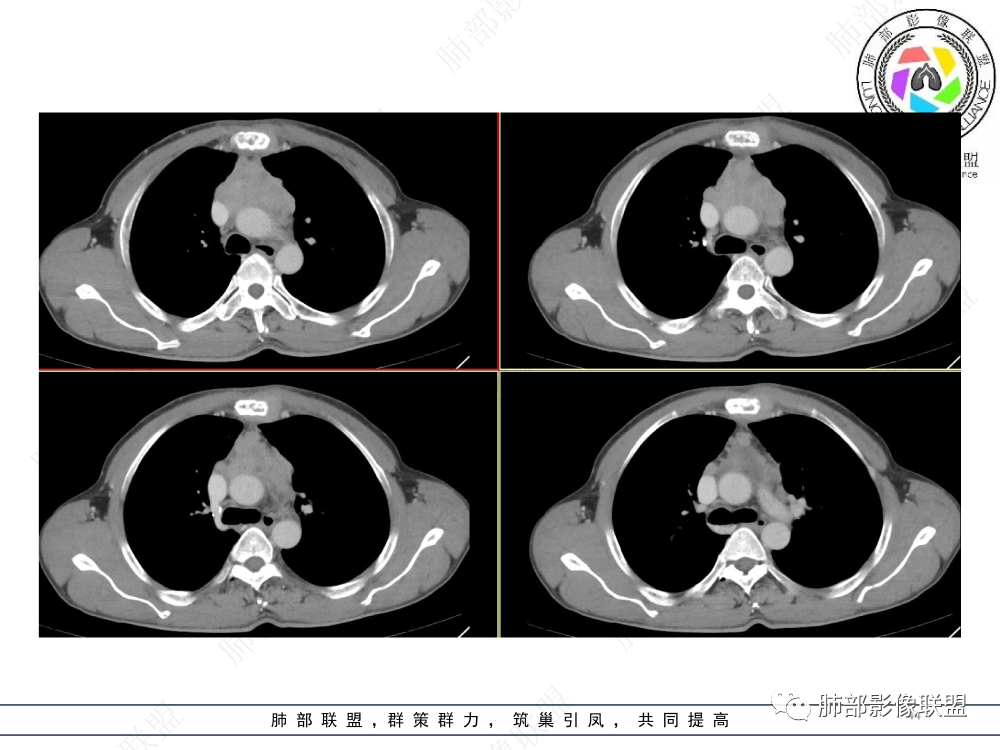

1.临床资料:中老年男性,病史较长-8个月,主诉胸痛,实验室资料:乳酸脱氢酶(LDH)升高。

2.影像表现:前上纵隔较大肿块,密度不均,形态不规则,边界不清,有结节样突起,脂肪间隙显示不清。病灶侵犯左无名静脉及上腔静脉,其中左无名静脉闭塞(胸背部侧支循环明显,亦表明回流受阻)。增强后轻中度不均强化。坏死边界欠清晰。可见心包积液,提示心包受侵犯。右侧上叶及纵隔胸膜下结节影,疑胸膜肺转移可能。胸骨柄后缘皮质不完整,疑骨质破坏(未提供骨窗及矢状位图像)。左锁骨上可见肿大淋巴结。